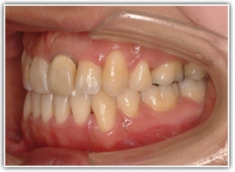

治療後(2年3ヶ月後)

骨格的な下顎前突の傾向は強くはありませんが、歯牙の状態によって反対咬合が認められます。LowTongue(低位舌)もあります。

舌位、気道、咽頭扁桃、口蓋扁桃、良好なEラインとプロファイルが得られております。

歯根のパラレリング(平行性)が獲得されております。

下顎8番は、両側抜歯済みです。

顎位は良好な状態です。